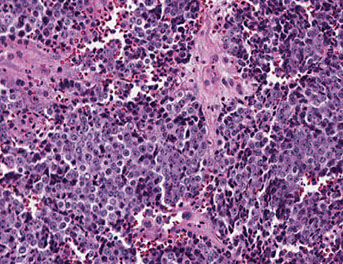

Small cell lung ca- SCLC

10-15% of lung ca's; MC NE ca

All are high grade (>11 mits per 10 hpf, highly malignant, widely metastatic, very aggressive, undifferentiated) - basically a high grade version of carcinoid

- see extensive pulmonary necrosis

- MCC SVC syndrome

- dont use term "oat cell ca" anymo

- Presents CENTRALLY with circumferential infiltration beneath the bronchial mucosa; rarely presents as an exophytic endobronchial lesion (which is usually seen c bronchial carcinoids)

May produce: ectopic ACTH / ADH; may cause Lambert-Eaton syndrome (autoabs against Ca2+ channels)

Sentral location

Histo: neuroendocrine Kulchitsky cells (small dark blue cell tumor) in sheets, salt n peppa chromatin c no nucleoli; crushed, high NC, nuclear molding, scant cytoplasm

- lots of necrosis and mits

IHC: (+) neuron-specific enolase, chromogranin, synaptophysin, CD57, TTF-1 (9/10), Cam5.2 and AE1/AE3 (punctate positivity)

- differentiated from carcinoids with a high mitotic rate (>20%, usually ~70%)***

- neg: Napsin A, CK7 (var), CK20, p63, CK903/5/6

- don't need stains to dx small cell ca (1/10 small cell ca's neg for all IHC; do need IHC for large cell dx)

Anti-apoptotic BCL-2 in 90%; L-MYC oncogene

Tx: Inoperable but responsive to chemo

Px: poor; usually met'd at time of discovery

- mean survival after dx: 1 year